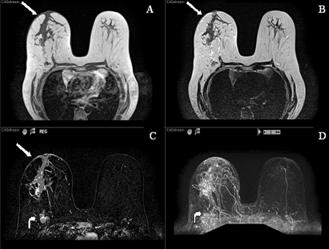

In October 2007, almost a year after her initial ovarian cancer diagnosis, the patient reported the new-onset of right breast edema. Although she had been previously followed for the right axillary lymphadenopathy, she had recently noticed an increase in erythema, thickness, and warmth of the skin of her right breast [Fig 1, 2]. She was treated with a 10-day course of antibiotics, with no change in symptoms. She then underwent an ultrasound of her breast that showed an ill-defined hypoechoic area in the right upper outer quadrant with multiple enlarged lymph nodes. A subsequent mammogram showed scattered fibroglandular densities and an area of architectural distortion with a few small punctate calcifications. Her gynecologic oncologist performed a fine-needle aspiration of the breast, which showed cells consistent with adenocarcinoma. She then underwent a second bilateral breast MRI, which confirmed the presence of an area of heterogeneous enhancement measuring 8 x 4 cm, highly suggestive of cancer, with areas suspicious for tumoral extension to the chest wall [Fig 3, 4].

Figure 3

MR images (T1, T2, post-contrast subtracted and MIP) demonstrating a large segmental area of heterogeneous enhancement in the right central breast. There is also abnormal skin enhancement, thickening and edema (straight arrows) consistent with inflammatory changes related to dermal lymphatic involvement. Significant right axillary lymphadenopathy is also present (curved arrow).

Figure 4

Post contrast subtracted with CAD stream MR image shows a 7.8 cm x 4.2 cm heterogeneously enhancing mass containing several foci of rapid washout (Type III kinetics) compatible with carcinoma.